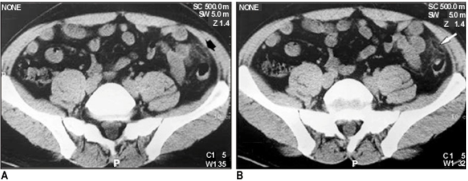

Um médico radiologista está de sobreaviso e recebe a ligação do plantonista da cirurgia geral para avaliar a tomografia de paciente feminino, 60 anos, com queixa de dor abdominal baixa há 1 dia. De acordo com as seguintes imagens, qual é o diagnóstico mais provável?